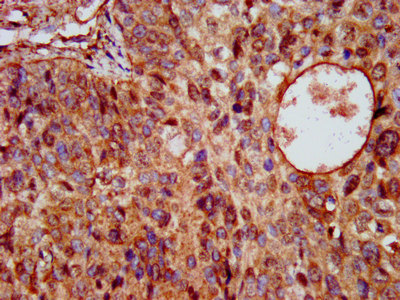

IHC image of CSB-PA22569A0Rb diluted at 1:200 and staining in paraffin-embedded human glioma performed on a Leica BondTM system. After dewaxing and hydration, antigen retrieval was mediated by high pressure in a citrate buffer (pH 6.0). Section was blocked with 10% normal goat serum 30min at RT. Then primary antibody (1% BSA) was incubated at 4°C overnight. The primary is detected by a biotinylated secondary antibody and visualized using an HRP conjugated SP system.

IHC image of CSB-PA22569A0Rb diluted at 1:200 and staining in paraffin-embedded human cervical cancer performed on a Leica BondTM system. After dewaxing and hydration, antigen retrieval was mediated by high pressure in a citrate buffer (pH 6.0). Section was blocked with 10% normal goat serum 30min at RT. Then primary antibody (1% BSA) was incubated at 4°C overnight. The primary is detected by a biotinylated secondary antibody and visualized using an HRP conjugated SP system.